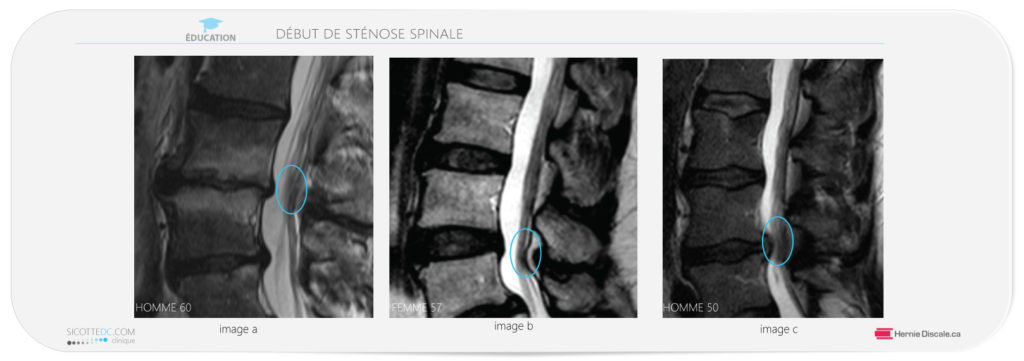

LA MEILLEURS FAÇON DE DIAGNOSTIQUER LA STÉNOSE SPINALE

Parmi les tests d’imagerie les plus prometteurs pour déceler la sténose spinale lombaire, on identifie l’imagerie par résonance magnétique (IRM), mais en évitant la myélographie, qui est invasive et n’offre pas une exactitude diagnostique plus élevée.

Les signes cliniques les plus révélateurs sont : une douleur irradiante à la jambe qui se trouve empirée par la station debout; l’absence de douleur en position assise; la réduction des symptômes en position de flexion avant; et enfin une démarche aux pieds écartés.